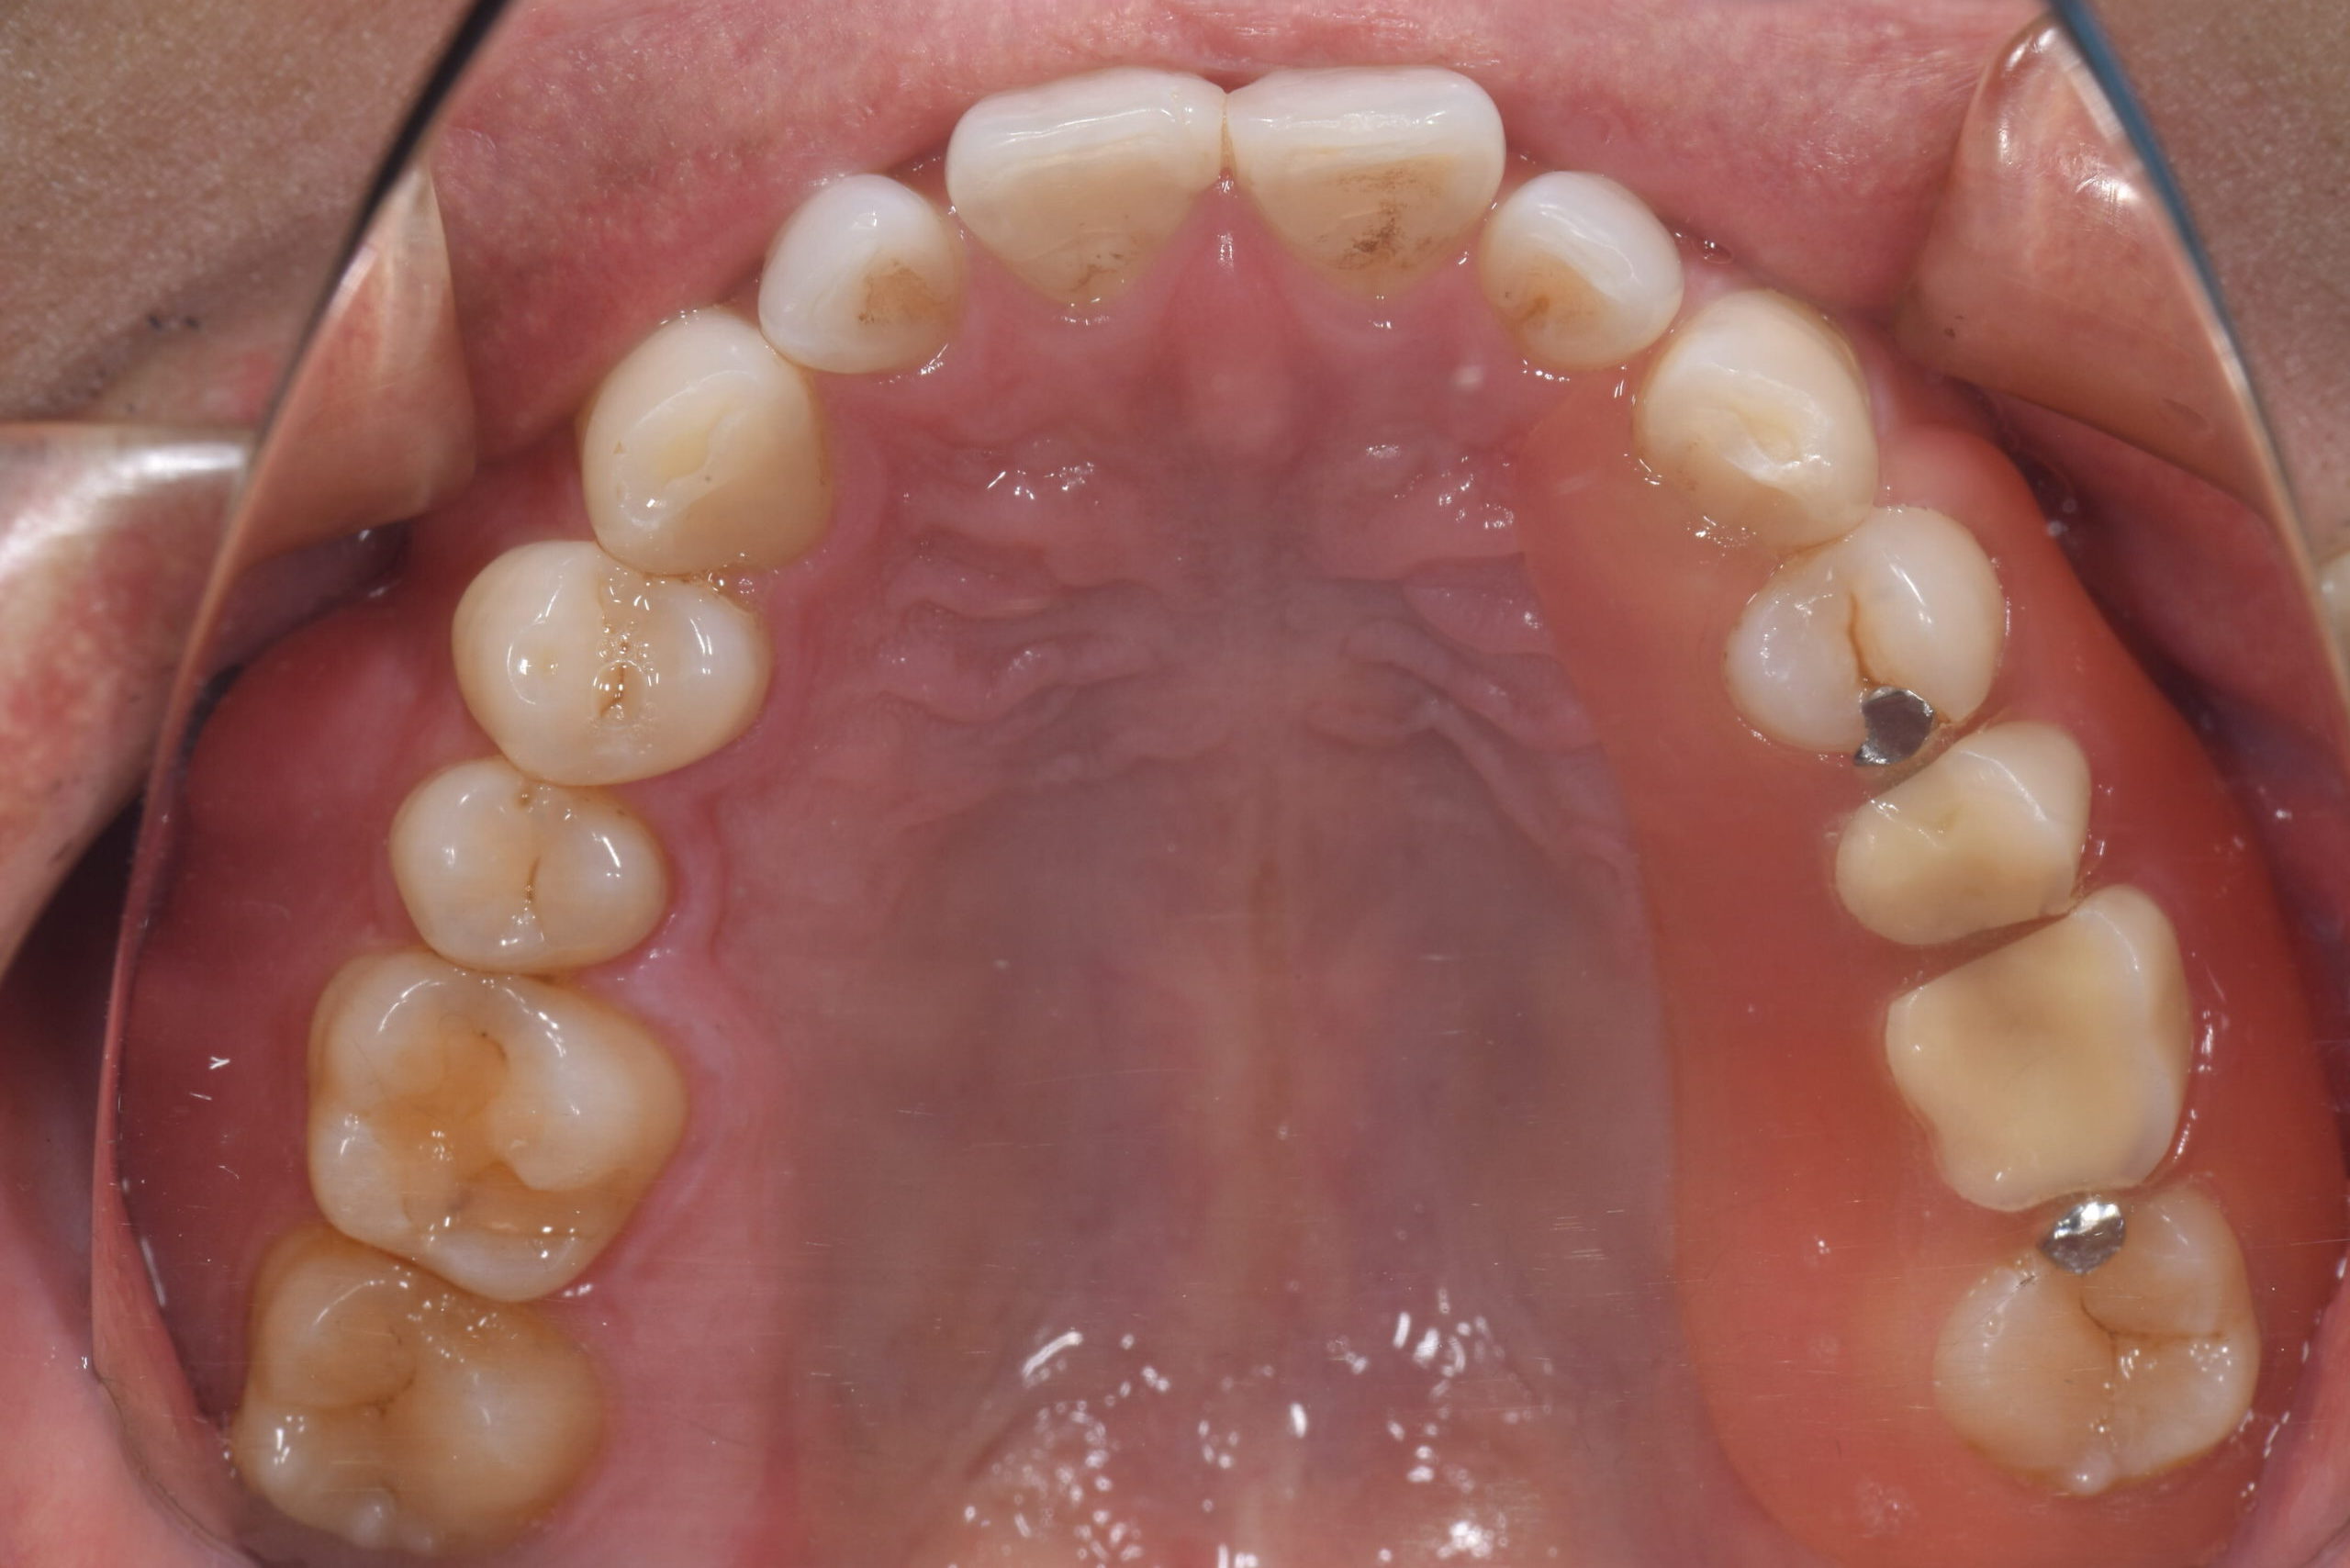

Before -上顎-

After -上顎-

| 施術内容 | 金属アレルギー予防を目的に、金属フリーの自費補綴へ変更。適合性・清掃性・審美性の向上が得られています。 |

|---|---|

| 治療期間 | 約4ヶ月 |

| 費用 | オールセラミッククラウン 264,000円 オールセラミックインレー ハイブリットインレー 275,000円 |

| リスク・副作用 | 治療にともない、歯の破折や歯質の削合、場合によっては抜歯が必要となることがあります。また、金属や補綴物を除去する際に、完全に除去できない場合もあります。 |